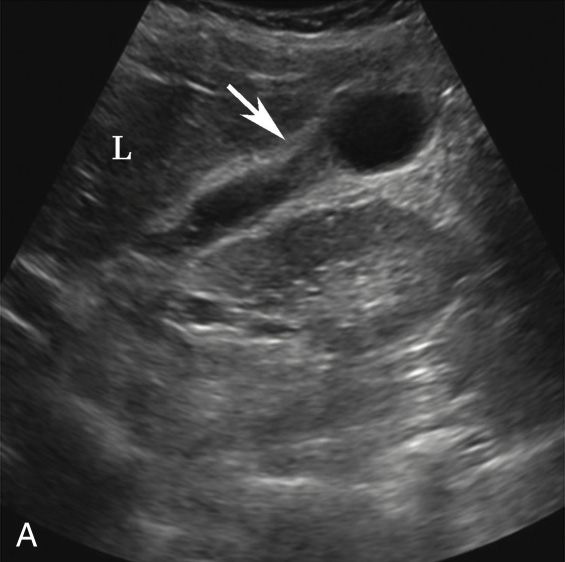

(2)节段型胆囊腺肌症:

好发于胆囊体部,胆囊壁呈节段型增厚,向腔内突入,灰阶超声图像呈“三角征”(图2-4-2)。

图2-4-2 节段型胆囊腺肌症灰阶超声图像

A.灰阶超声显示胆囊体部壁增厚(箭头所示),呈葫芦形;B.采用高频探头显示增厚处胆囊壁(箭头所示)